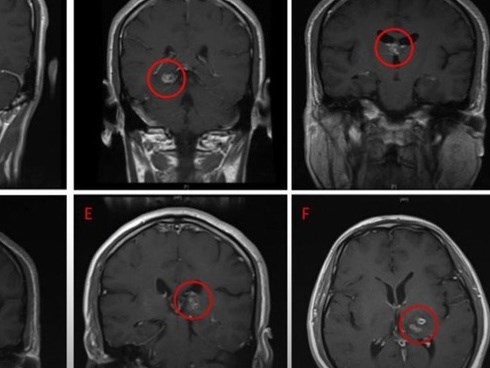

Ổ sán khổng lồ trong não khiến người đàn ông suy giảm trí nhớ nhanh đến kì lạ, tứ chi giảm vận động

Vừa qua, Khoa Ngoại Thần kinh - Bệnh viện đa khoa tỉnh Phú Thọ tiếp nhận một ca bệnh bị sán làm tổ lớn trong não.